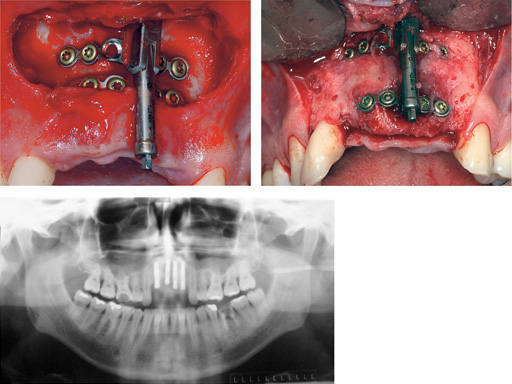

Distraction of a fibula flap in the mandibular body after tumor resection. The additional pin provides stabilization.

Maxillary distraction in a 34-year-old male after periodontal disease.